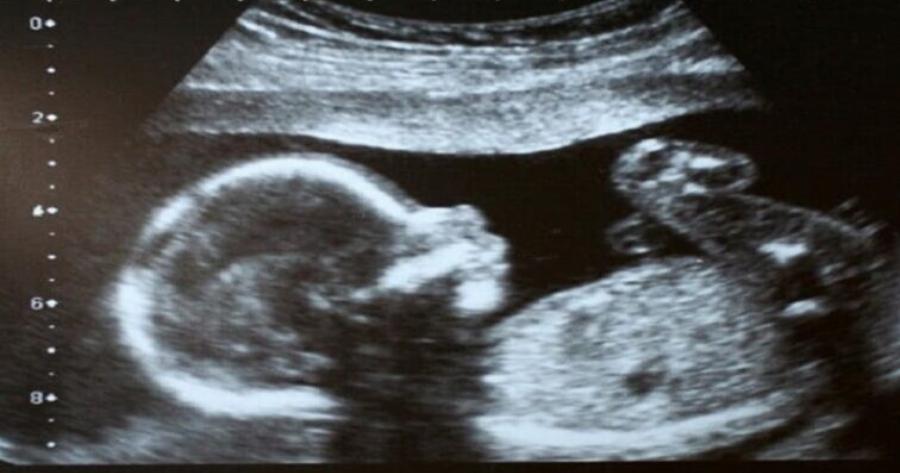

Η Έιμι Πούλ όταν ήταν έγκυος είδε το υπερηχογράφημα των 20 εβδομάδων της, και παρατήρησε ότι κάτι δεν πήγαινε καλά. Όταν είδε τη μύτη του μωρού της…έμεινε άναυδη από τον τρόμο!

Οι γιατροί επιβεβαίωσαν αργότερα, ότι ο γιος της είχε «απροσδόκητα μαλακό ιστό» που μεγάλωνε στο πρόσωπό του.